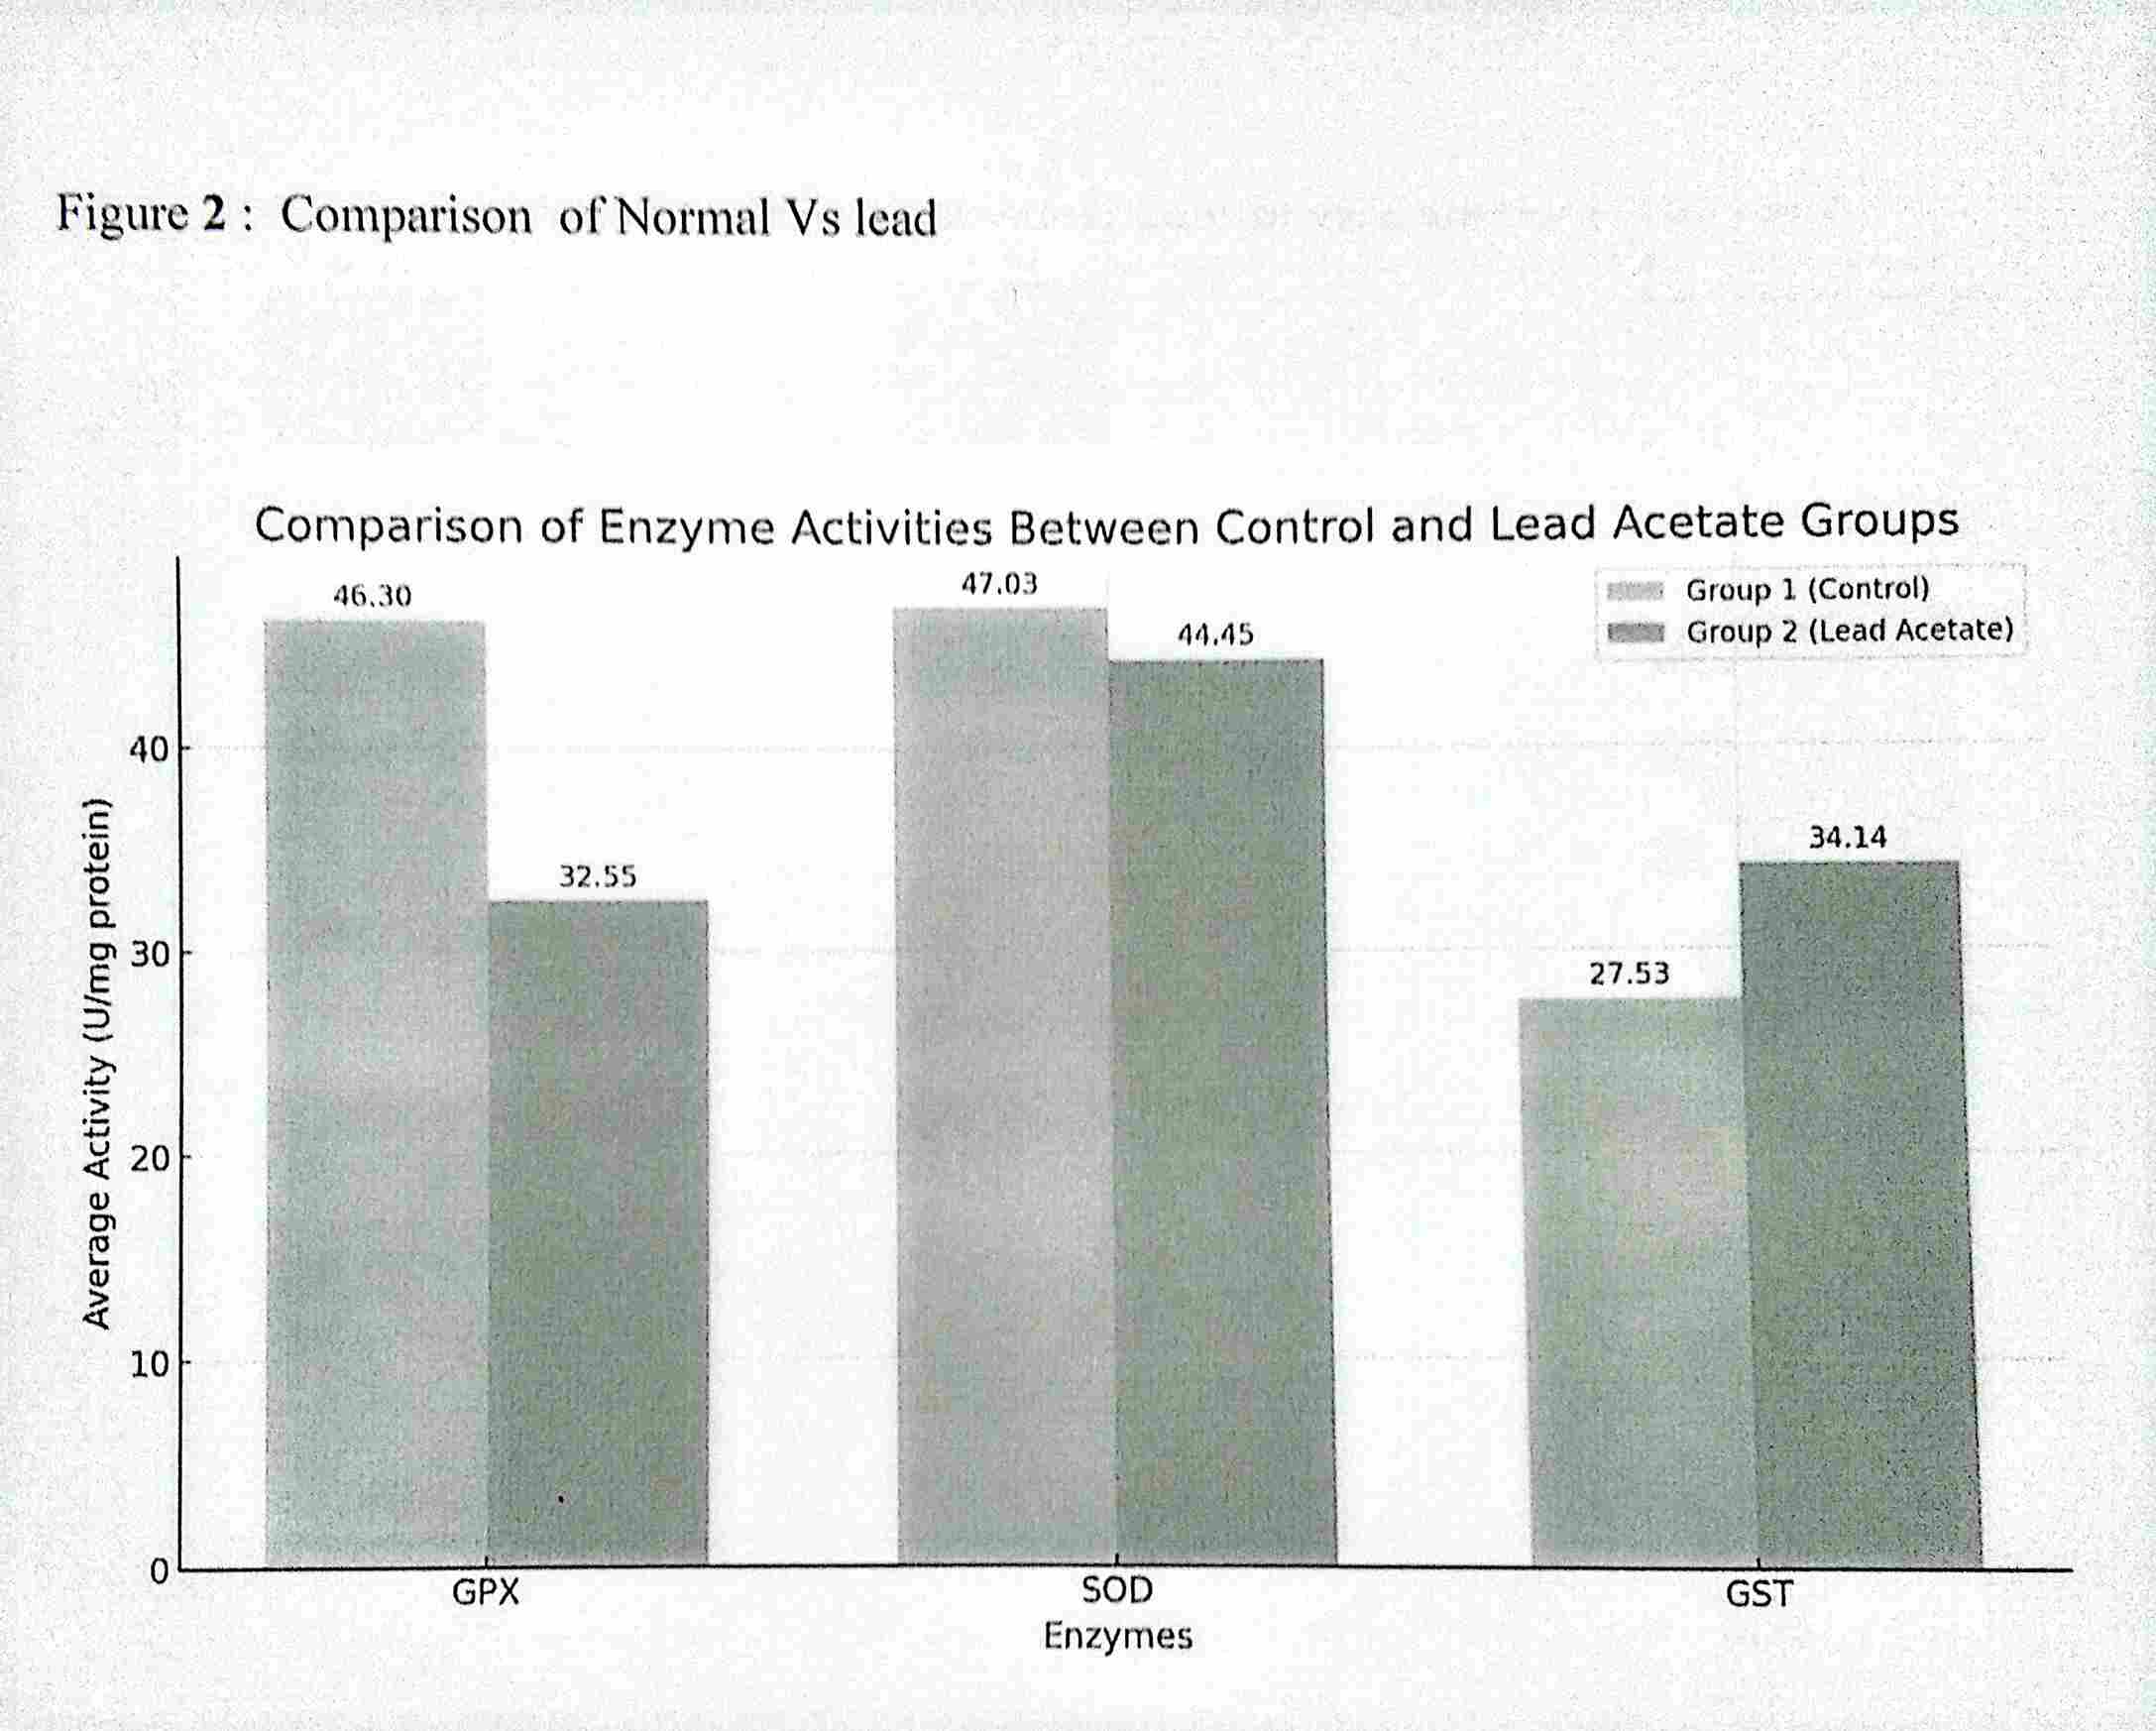

Comparative Analysis of Gastrointestinal Motility in Lead, Cadmium, and Mercury Exposed Wistar Rats

Effect of Hydro Ethanolic Seed Extract of Datura Metel on the Histology and Biochemistry of Liver Tissue of Sprague Dawley Rats